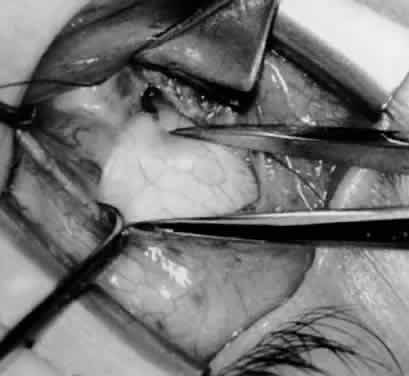

Fig. 11. Sutures are placed into the insertion of the inferior oblique muscle before it is sectioned from the globe for the recession procedure.

Fig. 12. An Aebli scissor is placed beneath the inferior oblique muscle insertion before it is sectioned from the globe.

Fig. 13. The inferior oblique muscle is sectioned from the globe. A preplaced 6-0 Vicryl suture is attached to the insertion.

Fig. 14. The inferior temporal vortex vein, 8 mm posterior to the temporal insertion of the inferior rectus muscle, is held on a Green muscle hook.

Fig. 15. The placement of sutures within the sclera for a recession procedure of 10 mm. The anterior suture is placed 3 mm temporal and 2 mm posterior to the lateral insertion of the inferior rectus muscle, and the posterior suture is placed 3 mm further posteriorly.

Fig. 16. Two sutures straddle the inferior temporal vortex vein insertion for a 14-mm recession procedure.

Fig. 17. Knots are tied to show the placement. The inferior oblique muscle is held on a Stevens muscle hook.

Fig. 18. The final position, with the inferior oblique muscle recessed 10 mm. The inferior rectus muscle is retracted with a Green muscle hook. As described in the text, the 14-mm recession would place the inferior oblique muscle over the inferior temporal vortex vein, and the 6-mm recession would place the inferior oblique muscle anterior and nasal to this position.

Fig. 19. A 14-mm inferior oblique muscle recession is placed over the inferior temporal vortex vein.

Fig. 20. Optional closure of the incision with a 6-0 Vicryl suture. The incision may be allowed to heal without a suture.

In comparing the various weakening procedures, Parks2,11 concluded that the recession procedure was superior (Figs. 120). The major advantage of the recession is that it allows the weakening procedure to be titrated according to the severity of the overaction. For 1+ overaction, the inferior oblique muscle is recessed 6 mm; for 2+ overaction, 10 mm; and for 3+ overaction, 14 mm, which is the maximum recession. A double-armed 6-0 synthetic suture, such as polyglactin (Vicryl [J-562]*) with a half-circle spatula needle (S-28*), is placed within the insertion of the inferior oblique with a locked bite at the anterior and posterior border (see Fig. 11). With an Aebli scissor, the muscle is sectioned from the globe (see Fig. 12) and recessed 6 mm by placing the anterior suture 4 mm lateral to the lateral insertion of the inferior rectus muscle and the posterior suture 3 mm more laterally. The 10-mm recession (see Figs. 15, 17, 18, 20) requires placement of the anterior suture 2 mm temporal and 3 mm posterior to the temporal insertion of the inferior rectus muscle, with the posterior suture placed 3 mm more posteriorly. The 14-mm recession (see Figs. 14, 16, 19, 20) requires placement of the anterior and posterior sutures parallel to the inferior-temporal vortex vein, which usually is found 8 mm posterior to the temporal insertion of the inferior rectus muscle.